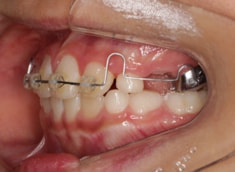

治療法:上顎拡大装置+フルパッシブブラケット(クリアスナップ)+フェイスマスク等

治療開始から6ヶ月後